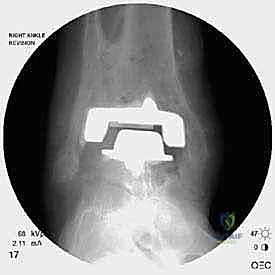

* مراجعة المفصل (Revision Arthroplasty): إزالة المفصل القديم وتركيب مفصل جديد مخصص للمراجعة (بسيقان معدنية أطول لضمان الثبات في العظم السليم).

تعتبر غرفة العمليات ساحة لإظهار البراعة الجراحية. عملية المراجعة تستغرق عادة من 3 إلى 5 ساعات وتتم عبر الخطوات المعقدة التالية:

الخطوة الخامسة: تركيب المفصل الجديد أو الدمج

يتم إدخال المفصل الجديد المخصص للمراجعة، والذي يحتوي غالباً على سيقان (Stems) تدخل عميقاً في عظمة الساق وعظمة الكاحل لضمان الثبات الميكانيكي. في حال وجود كسور في الكعب، يتم تثبيتها في هذه المرحلة.